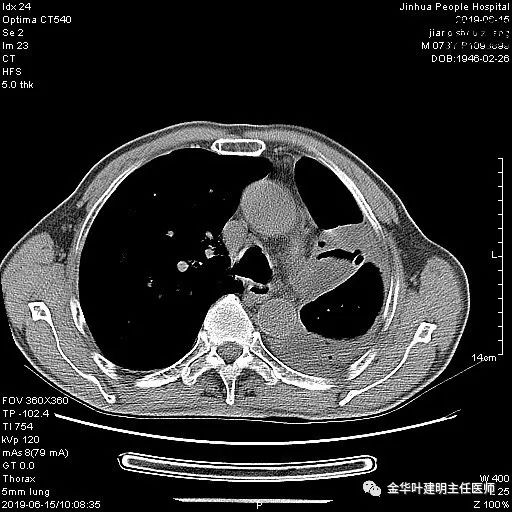

考虑左侧大量胸腔积液,遂进一步胸部CT检查:

以上是肺窗表现,下面为纵隔窗影像:

6.15上午:24小时胸管引流出血性液250ml;复查胸部CT示: